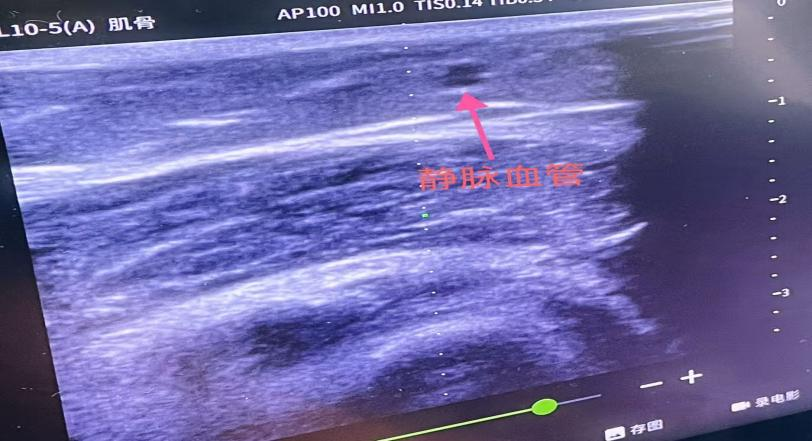

近日,敦化市医院麻醉科成功开展超声引导下静脉穿刺技术。这项技术借助高频超声探头实时显影,清晰呈现血管走行、管径及周围组织关系,彻底告别传统“盲穿”的经验依赖,通过精准控制穿刺深度与角度,大幅提升穿刺成功率与安全性,为患者带来更舒适的就医体验。

不久前,一名因骨折需接受全麻手术的患者就诊敦化市医院。该患者体重基数较大,外周血管较细且位置较深,加之术前禁食、术后疼痛导致血管收缩,不仅穿刺难度显著增加,且因手术时间较长、存在术中输血可能,必须建立稳定的大号静脉通路。为保障手术安全,在护士长指导下,护理团队迅速启用超声引导技术:探头轻触皮肤,屏幕上清晰锁定目标血管,医护人员精准调整穿刺角度与深度,一次成功置入大号留置针,稳稳筑牢术中补液、输血的“通路防线”,确保手术全程安全平稳。